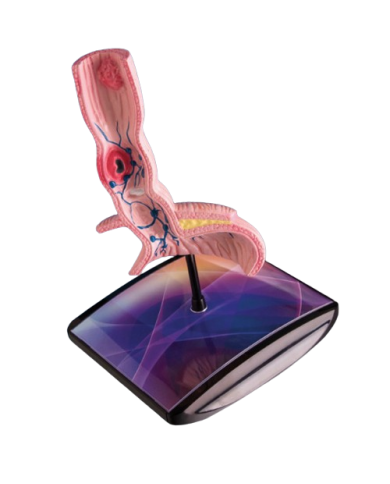

Modello anatomico PER FORNITURE CASE FARMACEUTICHE

Modello anatomico PER FORNITURE CASE FARMACEUTICHE

Modello anatomico PER FORNITURE CASE FARMACEUTICHE

Modello anatomico PER FORNITURE CASE FARMACEUTICHE

Modello anatomico PER FORNITURE CASE FARMACEUTICHE

Modello anatomico PER FORNITURE CASE FARMACEUTICHE

Modello anatomico PER FORNITURE CASE FARMACEUTICHE

Modello anatomico PER FORNITURE CASE FARMACEUTICHE

Modello anatomico PER FORNITURE CASE FARMACEUTICHE

Modello anatomico PER FORNITURE CASE FARMACEUTICHE

Modello anatomico PER FORNITURE CASE FARMACEUTICHE

Modello anatomico PER FORNITURE CASE FARMACEUTICHE

Modello anatomico PER FORNITURE CASE FARMACEUTICHE

Modello anatomico PER FORNITURE CASE FARMACEUTICHE

Modello anatomico PER FORNITURE CASE FARMACEUTICHE

Modello anatomico PER FORNITURE CASE FARMACEUTICHE

Modello anatomico PER FORNITURE CASE FARMACEUTICHE

Modello anatomico PER FORNITURE CASE FARMACEUTICHE

Modello anatomico PER FORNITURE CASE FARMACEUTICHE

Modello anatomico PER FORNITURE CASE FARMACEUTICHE

Modello anatomico PER FORNITURE CASE FARMACEUTICHE

Modello anatomico PER FORNITURE CASE FARMACEUTICHE